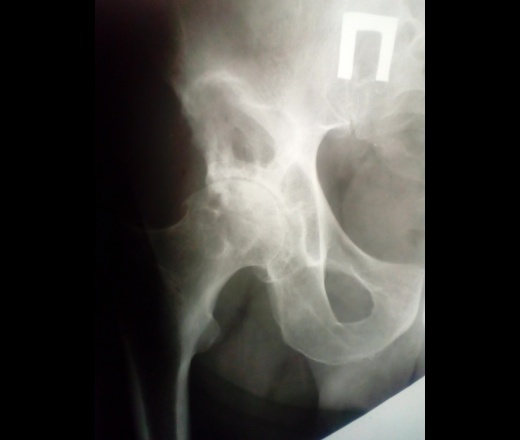

М. 1948 г.р. Жалобы на похудение, боли в правой половине таза.

Описал как участок литической деструкции передней нижней подвздошной ости, бобовидной формы, со склеротическим валом. В заключении написал mts, но мучают сомнения. Ваши мнения, коллеги?

Выраженные признаки коксартроза справа, вероятно такая гигантская кистовидная перестройка. Отправила бы на СКТ.

Ну раз все предпологают) Ложная вертлужная впадина , вследствие длительносуществующего вывиха головки бедренной кости.

Нет ни каких данных за зло. У зла как правило нет четкого контура. Склеротический ободок- означает медленный рост. Скорее всего подвывих, артроз, кистовидные просветления(проявление артроза).

Ну вот на первый взгляд зла не вижу.Такие непривычные дегенеративно-дистрофические изменения в смежных отделах костей,образующих сустав. Там ведь не один "литический очаг",а несколько. Расцениваю их как крупную кистовидную пперестройку при длительно существующем подвывихе, артрозные дела.Наверное, и мало двигался,щадил ногу. Могу и ошибаться.

А не характерны ли эти кистовидные изменения для пигментного виллонодулярного синовита?

Фиброзная дисплазия бедренной и подвздошной костей с формированием коксартроза.